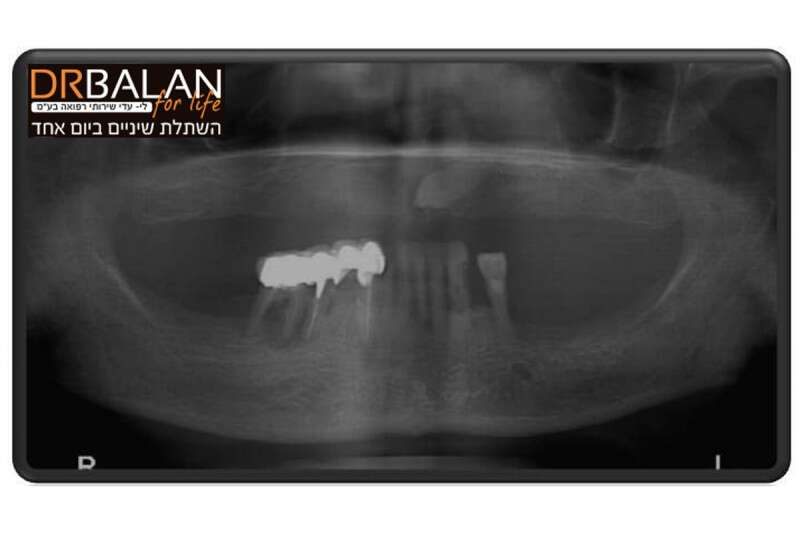

מצב של חוסר עצם קיצוני בלסת // מקור: drbalan.co.il

השתלת שיניים במקרה של חוסר עצם קיצוני בעזרת שתלים זיגומטיים ושתלי דיסק // מקור: drbalan.co.il